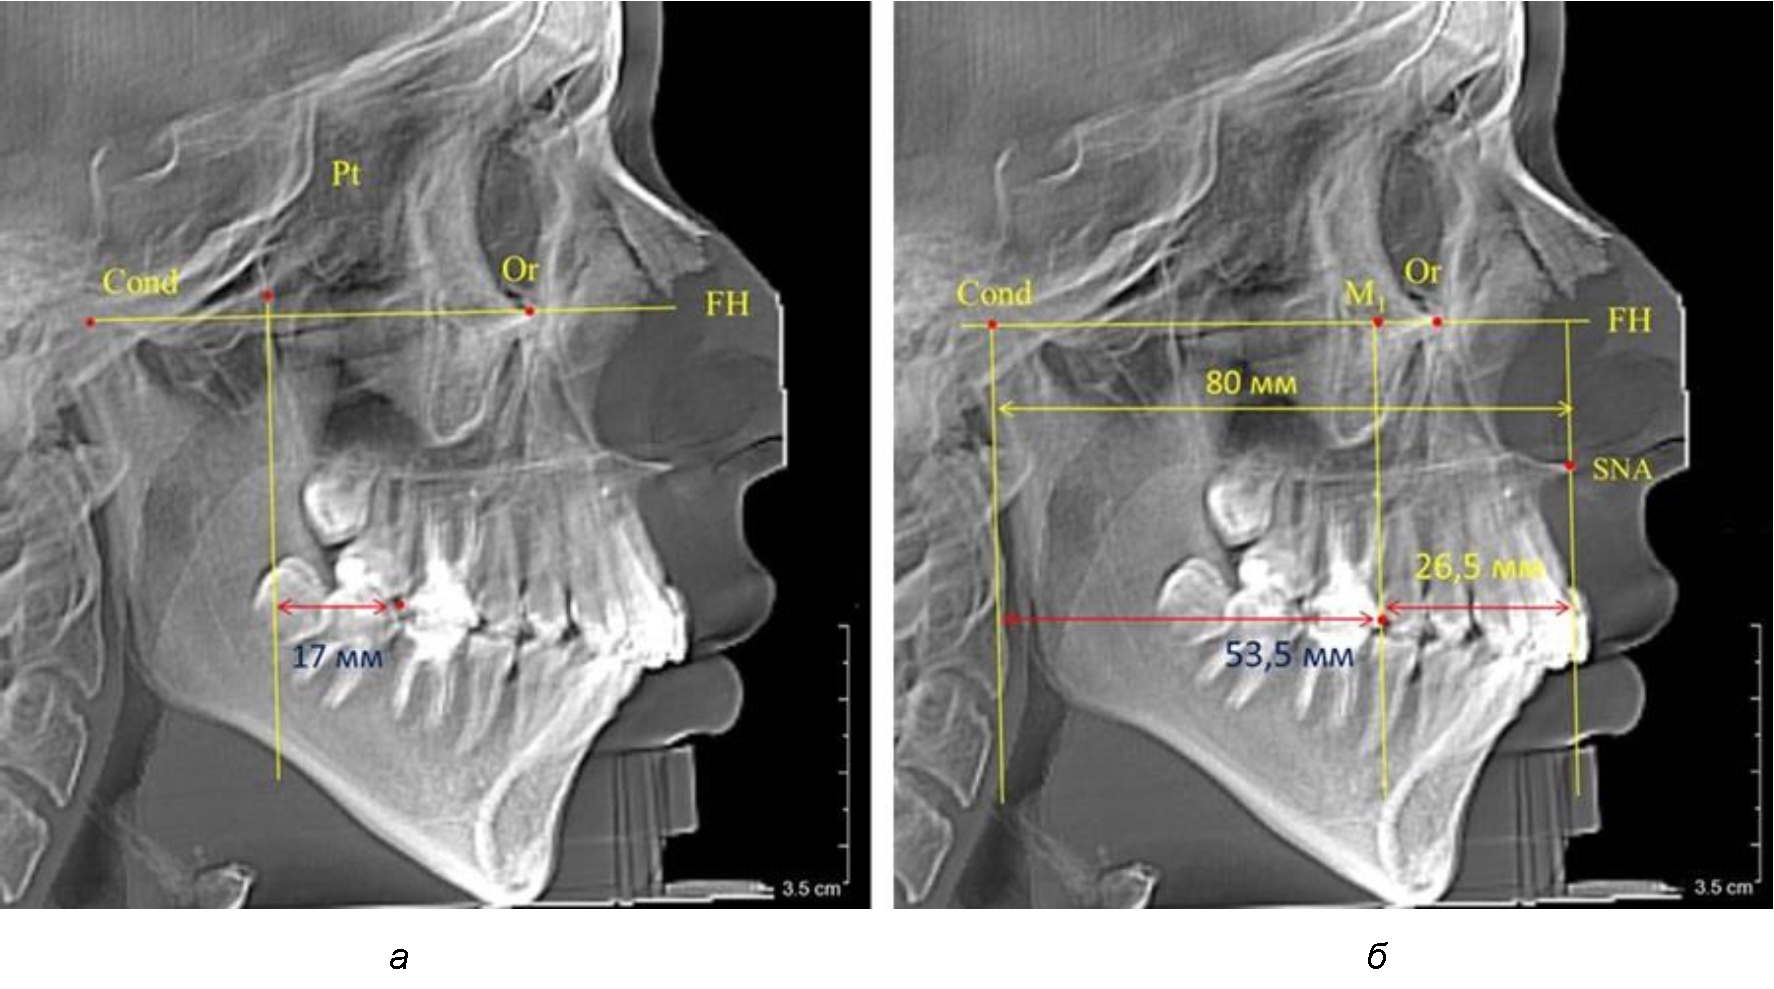

Рис. 6. Особенности положения первых моляров по R. E. McDonald (а) и по предложенному методу (б) у ребенка 16 лет

После прорезывания вторых постоянных моляров кондилярно-спинальный увеличивался до 80 мм.

Дистальная поверхность первого постоянного моляра отстояла от крыловидной вертикали на величину, составляющую около 18 мм, что, так же, как и в предыдущих периодах прикуса, было близким по значению к данным R. E. McDonald, а именно возраст, плюс 3 мм.

Обращает на себя внимание отношение глубины гнатического отдела лица к дистальному отделу, а именно к кондилярно-молярному расстоянию, которое, вне зависимости от сагиттальных размеров, составляло 1 : 1,5.

Рентгенограмма 16-летнего ребенка, с реперными линиями и анализируемыми линейными параметрами по двум используемым методам, представлена на рис. 6.